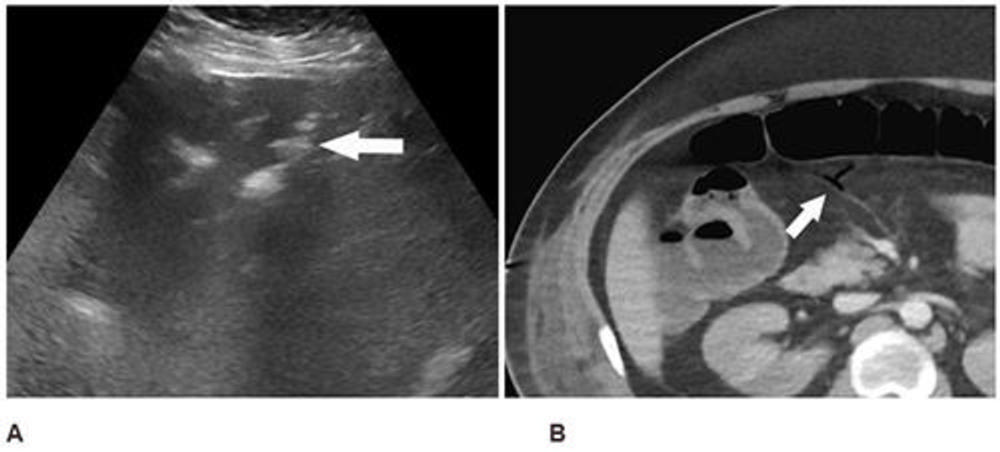

Figure 4. Abdominal ultrasound (A) performed for elevated liver enzymes in a 34-year-old man incidentally noted peripheral echogenic branching foci (arrow) with dirty shadowing (*), in keeping with portal venous gas. Subsequent CT abdomen and pelvis with IV contrast (B) confirmed portal venous gas and demonstrated gas in the transverse mesocolon vasculature (arrow). At laparotomy, patchy areas of yellow discoloration were identified on the antimesenteric aspect of the transverse colon of uncertain etiology. Second look laparotomy demonstrated yellow discoloration of the stomach and no ischemia.